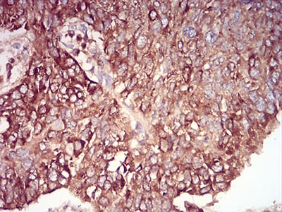

| AC3333 | Rab6b Mouse Monoclonal antibody[6D12E] | 100ug | $367 | 10days |

| AC3333 | Rab6b Mouse Monoclonal antibody[6D12E] | 200ug | $660.6 | 10days |